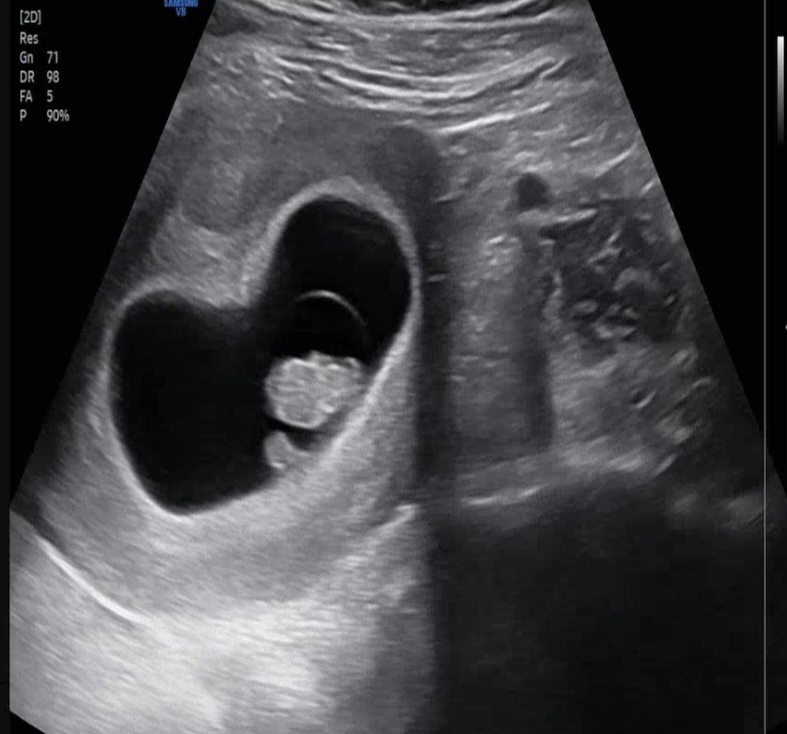

태아 옆에 있는 혹처럼 생긴건 뭘까요 아시는분ㅠ

난황이지 않을까요? 같이 찍히더라구요 ㅎㅎ

아 난황이군요..ㅋㅋ 모양이 혹같이 생겨서 놀랬어요..ㅠㅋㅋㅋ